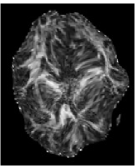

Trace and Mean Diffusivity: The total diffusivity is , and the mean diffusivity (MD) is equal to one third of . The MD measure serves as an indicator of brain maturation and/or injury, and provides the overall magnitude of water diffusion independent of anisotropy [21]. The MD map is shown in Figure 4(c), where higher values of average diffusion appear brighter.

Fractional Anisotropy (FA): FA serves as an indicator of the degree of water diffusion anisotropy independent of the overall water diffusion coefficient and is defined as

| (7) |

which is basically the normalized standard deviation of the eigenvalues. The values of FA vary from 0 to 1 with higher values corresponding to greater diffusion anisotropy. Figure 4(c) shows the FA map of the same slice as in Figure 4(a). The higher values of FA correspond to the WM regions containing densely packed fiber bundles that cause anisotropic diffusion by restricting water movement along the direction perpendicular to the fiber bundles.

![]() |

| (a) | (b) | (c) | (d) |